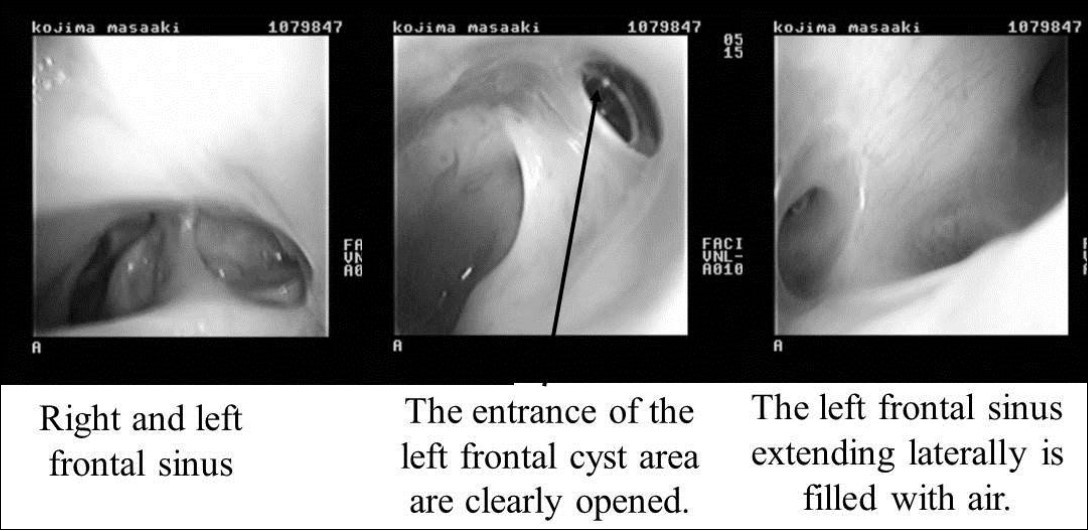

On April 16, 2008, reoperation was performed to place a ceramic implant, but some pus was found in the left lateral sinus. The lesion was debrided, the dead space was filled with muscle, and surgery was completed without ceramic implantation. On October 17, 2008, another surgery confirmed that the frontal sinus was clean, and a ceramic implant was placed. The postoperative course has been good, and as of May 2009, the frontal sinus extending laterally is filled with air (Figure 5, Figure 6).

Figure 6.Endoscopic findings after surgery. Right and left frontal sinuses. The entrance of the left frontal cyst area is clearly opened (black arrow). The left frontal sinus extending laterally is filled with air.

Endoscopic findings after surgery. Right and left frontal sinuses. The entrance of the left frontal cyst area is clearly opened (black arrow). The left frontal sinus extending laterally is filled with air.